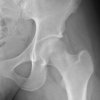

19 female, triathlete c/o groin pain. started after a spike in training load over a 2 month period. 60km a week bike, 40-50 km running, 2-3 swims. Exam Antalgic gait Pain with FADIR and IR of hip NAD on X-ray. x-ray MRI MRI – Coronal Views What is the pathophysiology of a stress fracture?